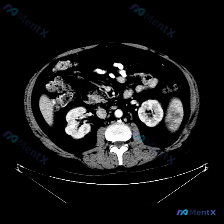

这是一幅腹部增强CT横断面图像(腹主动脉内见高密度对比剂充盈,提示动脉期或血管期)。

- 脾脏:形态大小正常,无肿大;脾实质密度均匀,未见明确占位、梗死灶或局灶性强化异常。

- 其他结构:双侧肾脏、部分肝脏、腹主动脉/下腔静脉、腹膜后脂肪间隙、腰大肌等,在所显示层面均未见明显异常。